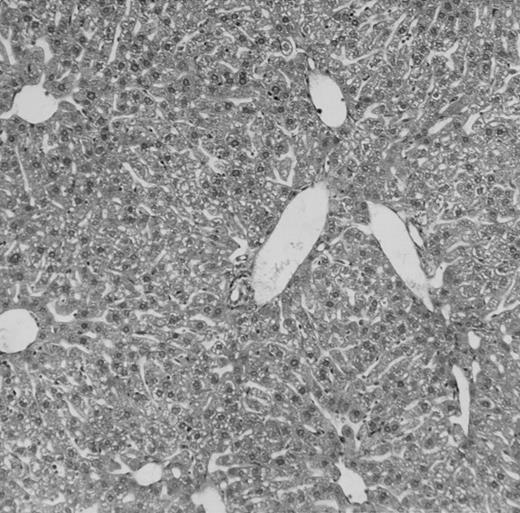

Histologic findings. Organs were collected at different times after BMT and tissue sections were stained with hematoxylin and eosin. Original magnifications for spleen (left) and liver (right) are ×40 and ×100, respectively. (A) B6 mice receiving FVB BM plus EpTK T cells. (B) Control group receiving BM only.

FVB BM-grafted B6 mice: a model of lethal GVHD.We developed a model of GVHD resulting in 100% mortality soon after BMT using FVB mice, a strain not previously used as BM donors in experimental allogeneic BMT. We tested different combinations of recipient irradiation doses, as well as injected BM cell and CD3+ peripheral T-cell numbers. When 10-Gy–irradiated B6 mice were reconstituted with 107 FVB BM cells, we observed prolonged survival, whereas all ungrafted animals died before day 16 (Fig 2). In these conditions, more than 98% of splenocytes were of donor origin (Fig 3A). When 107 CD3+ peripheral T cells from mice of FVB genetic background were added to the FVB BMT, all animals died of GVHD between days 7 and 34 (Fig 2). Similar results were obtained using either PBS-treated mice receiving EpTK or EpΔTK peripheral T cells or GCV-treated mice receiving FVB nontransgenic peripheral T cells. Notably, this observation also indicates that both TK- and ΔTK-expressing T cells in the absence of GCV are fully competent to induce a lethal GVHD. Histopathologic examination of spleen and liver of these animals showed characteristic GVHD lesions such as (1) architecture disruption, necrosis, and congestion in the spleen; (2) hepatic periportal necrosis; (3) mononuclear portal infiltrates; and (4) endothelialitis of portal or centrolobular veinules (Fig 4A). By comparison, B6 mice receiving only FVB BM had a normal histology (Fig 4B).

Using this delivery mode, we observed that mice receiving a 7-day GCV treatment initiated at the time of transplantation were protected from GVHD. At day 60, the survival rate was 100% in the GCV-treated group receiving EpTK CD3+ T cells, and was still 92% at the end of a 120 day follow-up (Fig 2A). Protected mice were apparently healthy, presented no visible skin lesions, and gained weight comparably to controls receiving only BM (data not shown). Hematologic reconstitution was analyzed by flow cytometry at different times from day 14 to day 212. Splenocytes of GCV-treated animals were of donor H-2q origin in the B-cell (B220+) and non–B-cell (B220−) compartments, the latter containing donor Thy1.1+ T cells but no recipient Thy1.2+ T cells (Fig 3B). Finally, histological analysis in these animals showed nodular architecture in the spleen and no significant hepatocyte necrosis or portal mononuclear cell infiltrates in the liver (not shown) and similar to control animals receiving only BM. Taken together, these data indicate that a GCV treatment, administered at the onset of allogeneic BMT and with a course as short as 7 days, abrogates GVHD and allows a full recovery from the lethal irradiation.